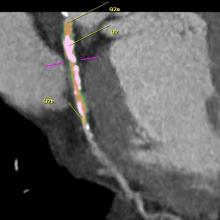

Trends and new technology for cardiac computed tomography angiography (CCTA) were highlighted during the 2012 Society of Cardiovascular CT (SCCT) annual scientific meeting in July in Baltimore, Md. Major topics included the development of fractional flow reserve (FFR)-CT imaging, perfusion imaging, imaging for transcatheter aortic valve replacement (TAVR) and analysis software advancements.